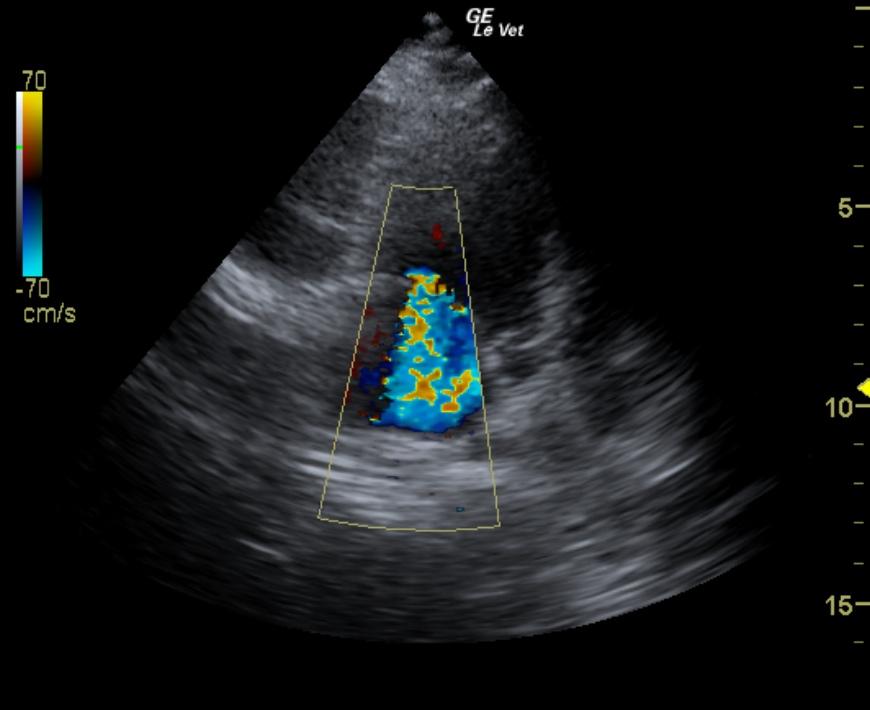

The echocardiogram for this dog presented excessive left atrial size expressed both in the LA/AO and LA max measurements. Left atrial content was anechoic and no evidence of “smoke” or thrombotic activity was noted. The atrial septum was deviated due to volume overload. The mitral valve apparatus demonstrated insufficiency on color flow and spectral Doppler. End point to septal separation was excessive owing to subnormal left ventricular contractility. The left ventricle demonstrated excessive volume (LVIDd measurement below). Ventricular function was subnormal expressed by the fractional shortening. The tricuspid valve presented moderate insufficiency. This is consistent with pulmonary hypertension with prominent right atrial enlargement. The right ventricle demonstrated subnormal kinesis. Rapid assessment of the hepatic veins and vena cava revealed no evidence of passive congestion. This presentation is most consistent AV valvular insufficiency and myocardial insufficiency (subnormal contractility in light of valvular insufficiency) with left sided volume overload and early congestive heart failure. Systemic factors such as hypothyroidism or systemic disease which negatively influence the myocardial contractility may also be playing a role in the presentation. Tricuspid insufficiency velocity was measured at 3.34 m/sec.

MRColorTRMeasurement